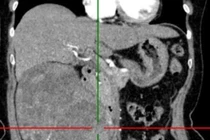

Loại bỏ khối u thận 1,2kg cho người bệnh 72 tuổi đau âm ỉ vùng lưng hông

U thận là bệnh lý nguy hiểm, thường diễn tiến âm thầm, ít triệu chứng rõ ràng, có thể xâm lấn, di căn, ảnh hưởng nghiêm trọng đến tính mạng.